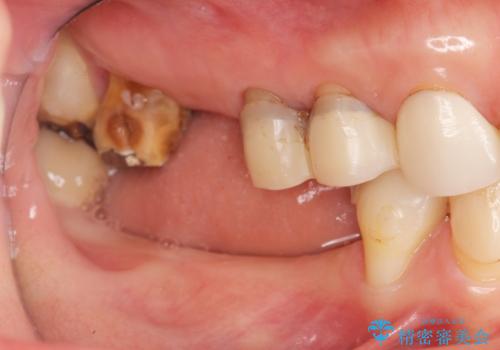

全顎 虫歯 インプラント治療

- 長年悩んでいる歯の見た目や欠損を全て治療したい、と希望され来院されました。

不適合やすり減ったクラウンを全て除去し、虫歯を丁寧に除去したのち精密なセラミック治療を行いました。

また失ってしまった奥歯についてはインプラントを用いて噛み合わせを確立する治療方針としました。